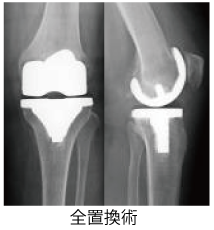

手術療法例-2 《人工関節置換術》

変形性膝関節症や関節リウマチによって傷んで変形した膝関節の表面を取り除いて、人工関節に置き換える手術です。

人工関節は、関節の滑らかな動きを再現できるようできています。手術翌日から立って歩くことができたり、入院期間も短くすむ場合が多いです。

ただし、正座がしにくくなったり、人工関節がすり減ったりゆるんだりすると入れ替えが必要となるため、定期的な検査が必要となります。